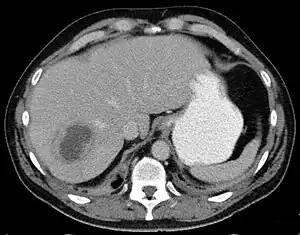

| Liver abscess on axial CT image: a hypodense lesion in the liver with peripherally enhancement. | |